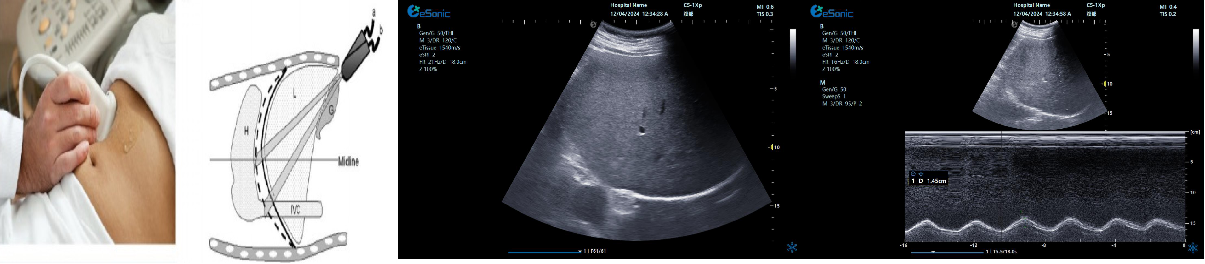

剑突下下腔静脉切面

扫查方法:在剑突下四腔心切面的基础上逆时针调整探头,直至标记指向被检者的头部,轻轻将探头向被检者右边倾斜。

超声声像图:显示右房,下腔静脉及肝静脉,注意观察下腔静脉及肝静脉有无扩张及搏动。